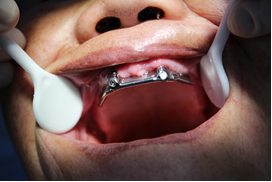

選復(fù)合基臺(tái)(上頜)/選復(fù)合基臺(tái)(下)

桿卡試戴(上頜)/桿卡試戴(下頜)

術(shù)后片/選復(fù)合基臺(tái)(下頜)

桿卡試戴(下頜)/活動(dòng)義齒(上頜)